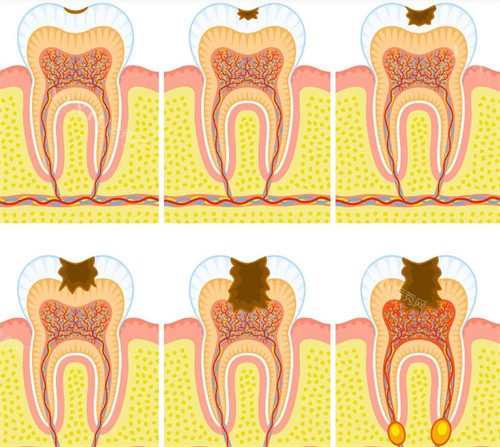

根据查询结果显示,高娅口腔确实具备合法执业资质,诊所登记类别为口腔专科门诊部,执业范围包括牙体牙髓病、牙周病、口腔修复等常规诊疗项目。

基础治疗:

补牙:200-500元/颗